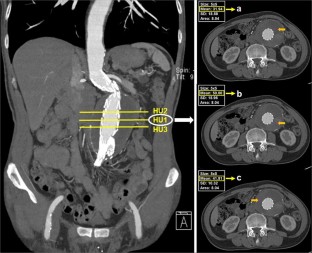

Fig. 1

HU:

Hounsfield unit